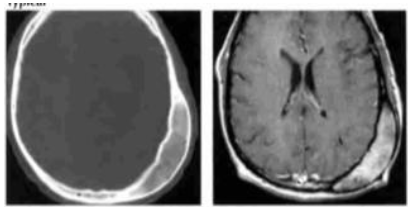

Analise as imagens abaixo.

Fonte: OSBORN, 2004.

As imagens acima são típicas de: